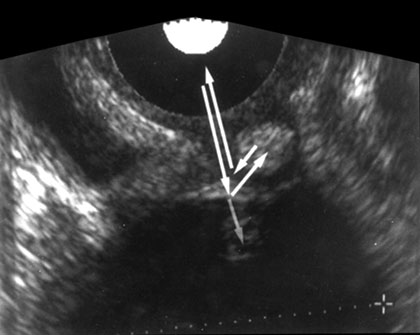

Reverberation

Reverberation occurs between transducer and a strong reflector or it can occur between two reflecting surfaces lying in the direction of beam. Here the reflector may be sufficiently strong to be detected by the instrument and to cause confusion on the display. The process by which they are produced is explained in Figure 1.21A. This result in the display of reflector that are not real.

Therefore not all echoes that originates at an acoustic interface return to the transducers without further reflection. If strongly reflecting boundaries are present sound wave can reflects back and forth before they eventually return to the transducer. This delay in registering the echo leads to reverberation. These reverberation echoes are projected as several parallel line placed beneath the real reflector at separate interval equal to separation between the transducer and real structure. And each subsequent echo is weaker than prior one, e.g. from intestinal gas to liver or ribs, urinary bladder or gallbladder. Reverberation can obscure tissue that lie behind the gas (Fig. 1.21B).

Fig. 1.21A: Reverberation (arrowheads) resulting from multiple reflection through a water path between a linear-array transducer (straight arrow) and the surface of an apple (curved arrow)

Fig. 1.21B: Echoes seen in the anterior portion of the urinary bladder due to reverberation artifacts